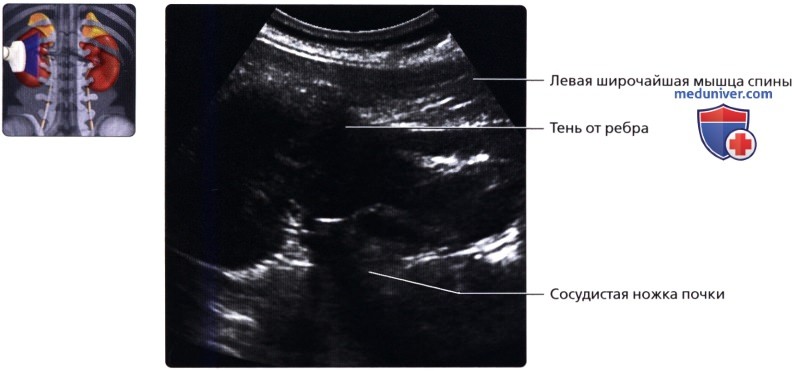

• Левая почка:

о Ее труднее визуализировать из-за газа в тонкой кишке и в селезеночном изгибе ободочной кишки

о Обычно левую почку проще визуализировать, используя заднебоковой эхографический доступ и попросив пациента немного повернуться вправо приподняв левый бок

о В сложных случаях полностью переверните пациента в положение лежа на правом боку, подложите подушку под его правый бок и попросите его поднять левую руку над головой:

— Для исследования верхнего полюса левой почки можно использовать селезенку как акустическое окно

о Задний эхографический доступ:

— Удобен при инвазивных процедурах (биопсия почки, нефростомия)

— Качество изображения может снижаться из-за теней от околопозвоночных мышц и ребер